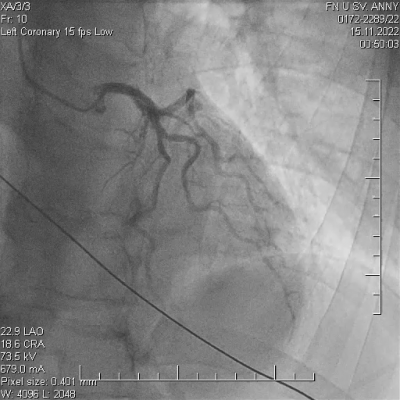

Pacient ve věku 45 let byl referován do našeho kardiocentra po mimonemocniční zástavě oběhu v terénu. Iniciálním nálezem na elektrokardiogramu (EKG)na místě zásahu byla fibrilace komor, byla poskytnuta rozšířená neodkladná resuscitace včetně orotracheální intubace a srdeční defibrilace s obnovením spontánní cirkulace do dvanácti minut. Emergentní selektivní koronarografie neprokázala žádnou významnou stenózu koronárních tepen (video 1, 2, 3), při ventrikulografii byla patrná globální hypokontraktilita levé komory, akcentovaná v oblasti spodní stěny srdeční s celkovou ejekční frakcí levé komory 30 %. V laboratorním nálezu byla s odstupem zjištěna elevace troponinu T stanoveného vysoce senzitivní metodou (hsTnT) – 3 500 ng/l (referenční rozmezí 14 ng/l) a elevovaný C-reaktivní protein (CRP) – 9,3 mg/l (referenční rozmezí 5 mg/l). Anamnéza pacienta zahrnuje bronchiální astma a nosní polypy s medikamentózní terapiísalmeterol/fluticason a omeprazol. Pacient je nekuřák, bez anamnézy abúzu drog.

Na základě těchto výsledků pacient podstoupil opakovanou koronární angiografii, kde byl oproti prvotnímu nálezu pozorován fokální spasmus na ramusinterventricularisanterior (RIA), s jeho úplným odezněním po intrakoronární aplikaci nitrátů (video 4, 5).

V následujících hodinách po výkonu dochází k rozvoji silných bolestí na hrudi jen s částečným odezněním po sublingválním podání nitrátů, na EKG jsou přítomny deprese úseku ST s následnými elevacemi úseku ST ve spodních svodech. Bolesti neustupují ani přes kontinuální intravenózní podávání nitrátů, pacient byl odeslán k provedení emergentní rekoronarografie (celkem třetí v pořadí) s nálezem mnohočetných kritických fokálních spasmů omezujících průtok ve více koronárních povodích (video 6, 7), s jejich postupným úplným odezněním po intrakoronární aplikaci nitrátů a diazepamu (video 8, 9).